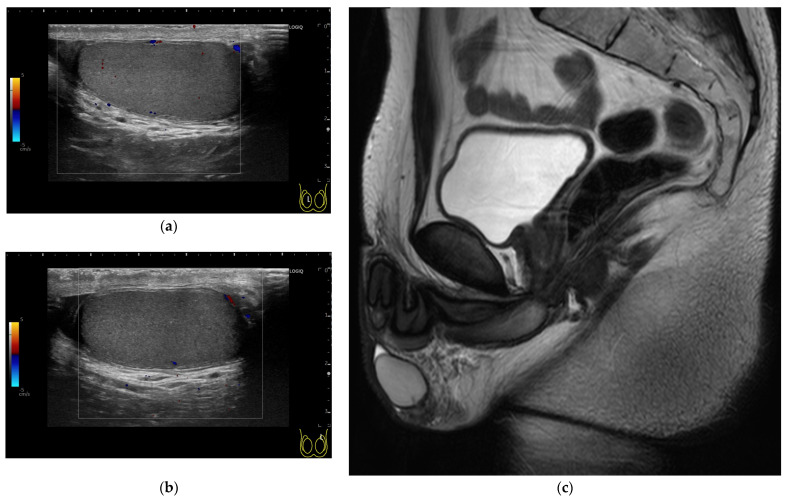

背景和临床意义:垂体腺瘤,也称为垂体神经内分泌肿瘤,在手术切除后发生促性腺功能低下(HH)的风险很大,对年轻患者的生育和性功能有深远的影响。病例介绍:我们报告一名来自日本农村的29岁男子,他在两次经蝶窦切除大垂体腺瘤后发展为严重HH和无精子症。尽管早期与神经外科团队接触,但由于缺乏现场内分泌专家和有限的当地肿瘤生育资源,生育管理被推迟。经过全面的内分泌评估和咨询,患者开始人绒毛膜促性腺激素和重组促卵泡激素联合治疗,性功能完全恢复,精液参数恢复正常,最终实现自然受孕,健康生育。基于这一真实案例,我们提供了当前垂体手术后HH的实际管理策略的叙述性回顾,包括激素刺激试验的效用,日本基于指南的补贴制度,以及激素替代的最佳实践方法。结论:该病例不仅强调了早期跨学科合作和术前咨询的必要性,而且强调了一例罕见的良性肿瘤患者接受的治疗没有解决其生育相关需求,强调了即使是非恶性肿瘤也应纳入术前咨询的考虑因素。加强区域肿瘤生育网络和提高保健提供者对保留生育选择的认识对于改善结果仍然至关重要。

Background and Clinical Significance: Pituitary adenomas, also termed pituitary neuroendocrine tumors, pose a significant risk of hypogonadotropic hypogonadism (HH) after surgical resection, with profound consequences for fertility and sexual function in young patients. Case Presentation: We present the case of a 29-year-old man from rural Japan who developed severe HH and azoospermia following two transsphenoidal resections for a large pituitary adenoma. Despite early engagement with neurosurgery teams, fertility management was delayed by the absence of on-site endocrinology expertise and limited local oncofertility resources. After comprehensive endocrine evaluation and counseling, the patient began combined human chorionic gonadotropin and recombinant follicle-stimulating hormone therapy, resulting in full recovery of sexual function and normalization of semen parameters, ultimately leading to spontaneous conception and the birth of a healthy child. Building on this real-world case, we provide a narrative review of current practical management strategies for HH after pituitary surgery, including the utility of hormone-stimulation tests, Japanese guideline-based subsidy systems, and best-practice approaches to hormonal replacement. Conclusions: This case underscores not only the necessity for early, interdisciplinary collaboration and preoperative counseling but also highlights a rare instance in which a patient with a benign tumor received care that did not address his fertility-related needs, emphasizing that such considerations should be integrated into preoperative counseling even for non-malignant conditions. Strengthening regional oncofertility networks and improving healthcare providers' awareness of fertility-preservation options remain essential for improving outcomes.